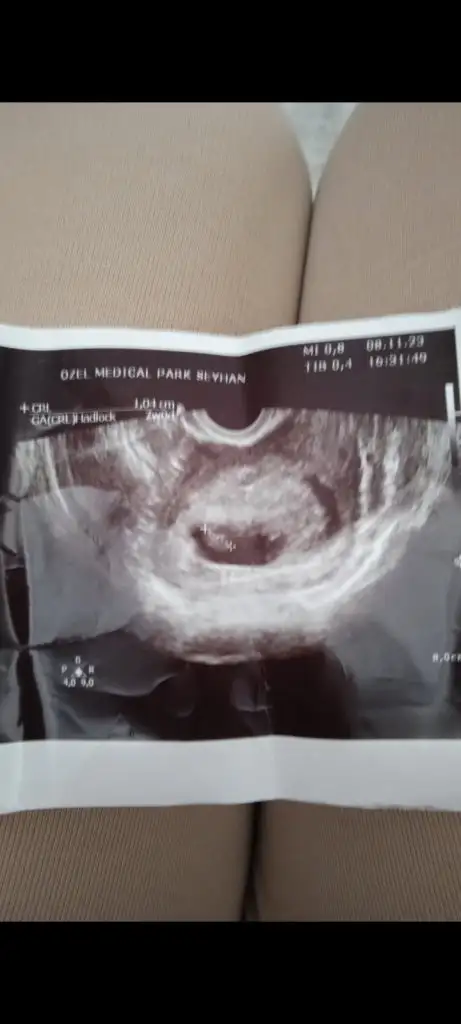

Bana da bakar mısınız vajinal ultrason

Eklentiler

• Screenshot_2023-11-12-22-15-00-033_com.miui.gallery.webp

Screenshot_2023-11-12-22-15-00-033_com.miui.gallery.webp

15,6 KB · Görüntüleme: 102